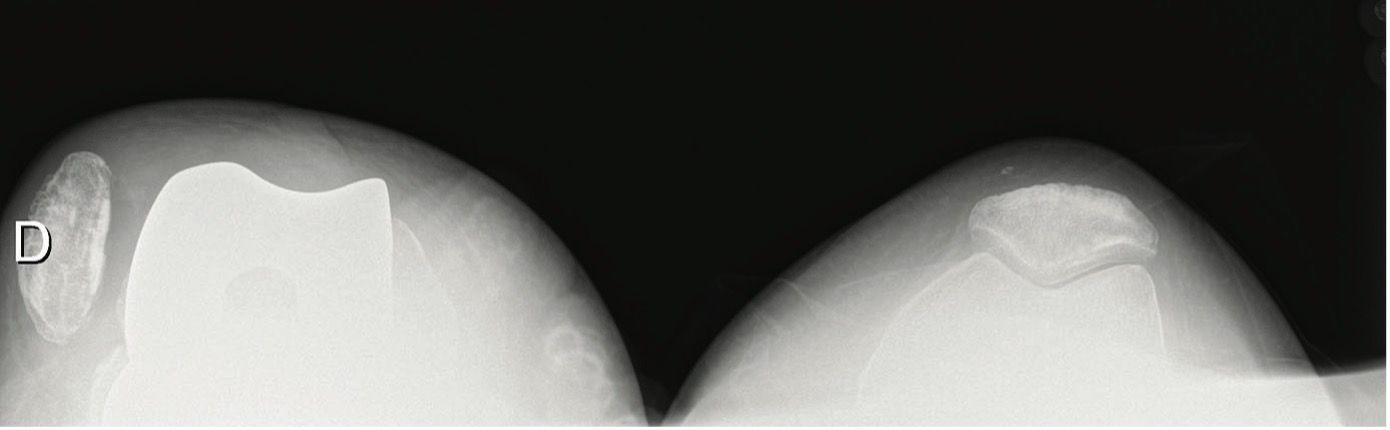

These clinical signs will help guide the subsequent radiology examination, which should begin with plain images (AP, lateral and axial view of the patella flexed at 45°). The diagnosis is positive when the patella is partially or totally dislocated. The differential diagnosis includes patellar loosening, patellar fracture, and extensor apparatus disruption.

With a positive diagnosis of PFI, the possible aetiology should be further evaluated by using plain x-rays for mediolateral positioning, implant size and limb alignment. Rotational malalignment can be assumed but needs confirmation with CT scan.

These patients have total or partial lateral dislocation of the patella (Fig. 1). The cause is rotational malalignment of the femur and/or tibia implant (Fig. 2) or severe torsional limb malalignment with increased femur anteversion or excessive tibia internal rotation or both.

Patellar tilt is relatively common in descriptive studies.[17] It can cause painful impingement between the lateral patellar facet and femoral implant,[18] in turn due to improper patellar preparation (Figs. 3 & 4) or after medial approach with dehiscence of the capsular closure.[19]